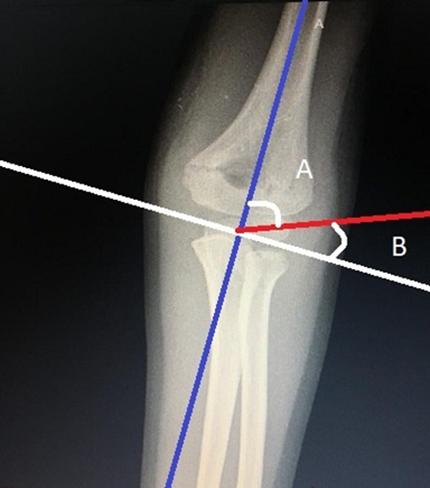

Para determinar el grado de desplazamiento en varo que presenta la fractura se utiliza el ángulo de Baumann, que se mide en la radiografía AP y tiene dos definiciones dependiendo del autor. Para algunos, está formado por la intersección de la línea media de la diáfisis del húmero con la línea fisiaria del cóndilo lateral o del capitellum, para un valor normal entre 64° y 81° (con un promedio de 72°)10,22,23. Para otros, el grado de desplazamiento sería el ángulo complementario al anterior, es decir, formado por una perpendicular a línea media de la diáfisis humeral, que intercepta igualmente la línea fisiaria del cóndilo lateral. En este caso, su valor normal sería entre 9° y 26° (Figura 6)2,3. Por tener un rango amplio de normalidad, es necesario compararlo con el codo contralateral, pues una variación anormal indicaría un colapso de la columna medial del húmero distal y por ende una deformidad en varo.